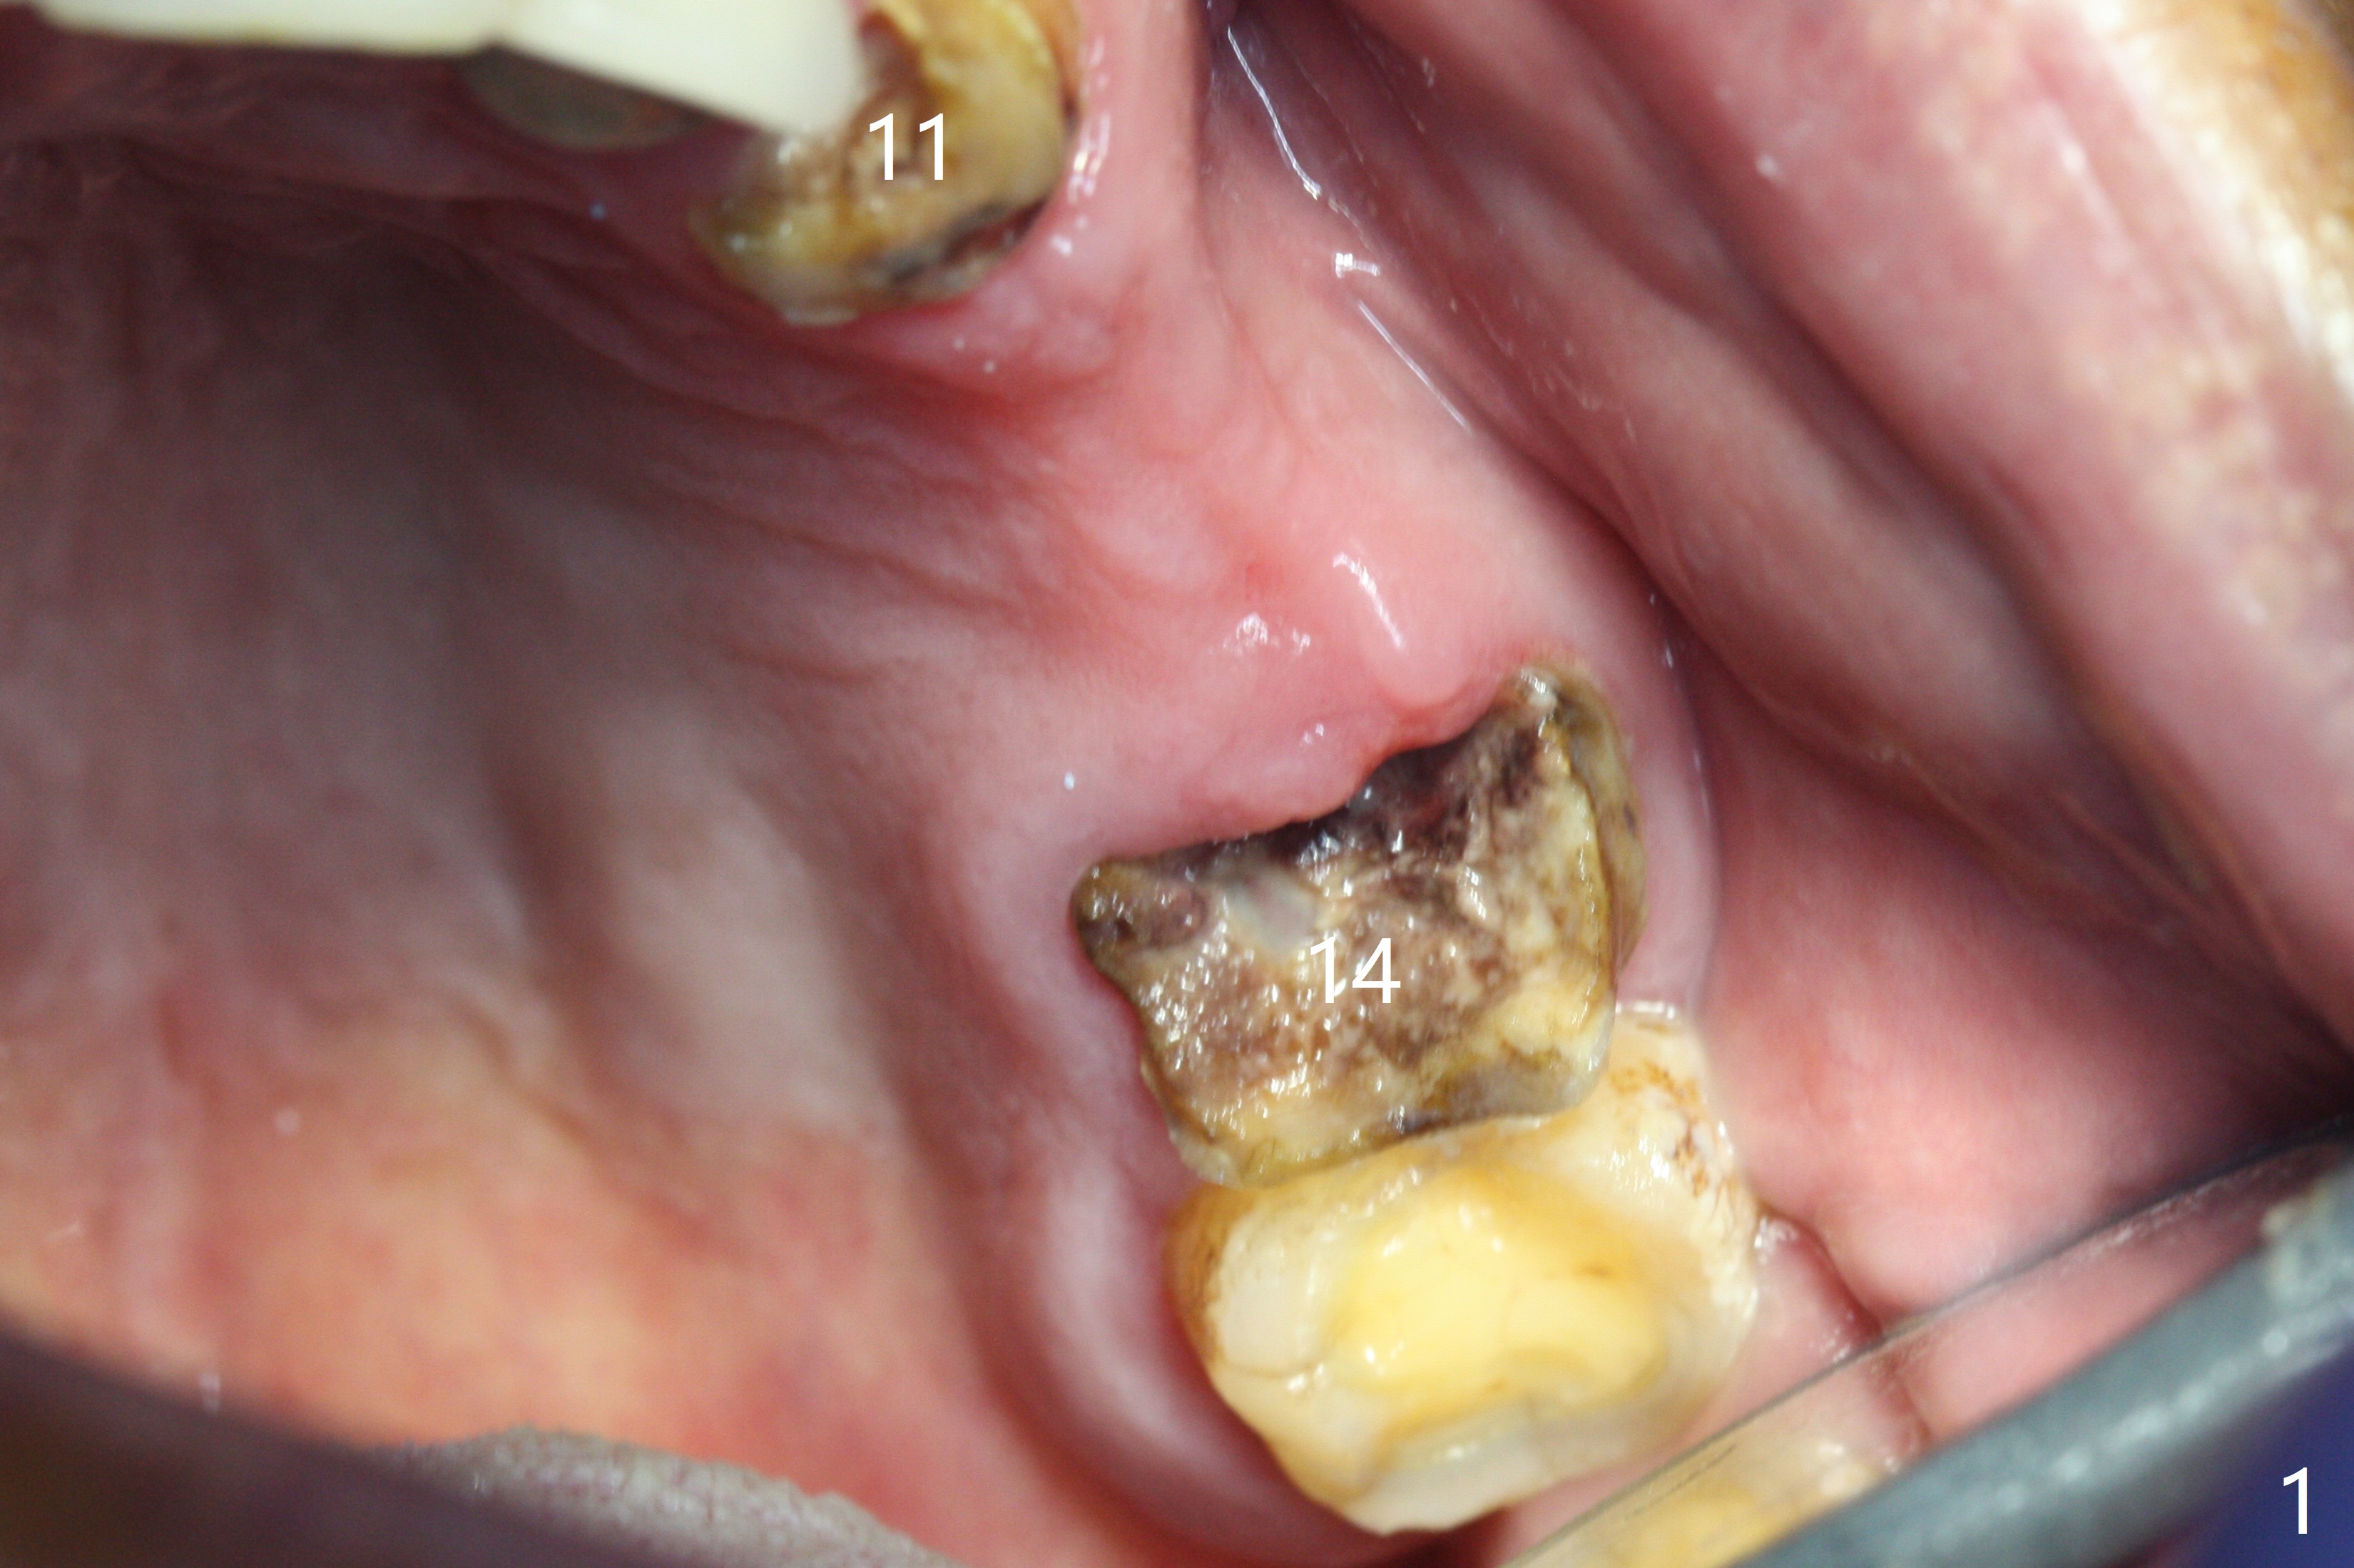

The edentulous ridge is narrow between the residual roots of #11 and 14 (Fig.1). Since the bone density is low in the edentulous area, DIO bone expanders are used (e.g., #1 (1/1.6 mm) Fig.2) after 1.2 mm initial drill. A 2x14(2) mm 1-piece implant is placed at #12 with 4 mm ridge width, while a 3x10 (2) mm dummy implant is partially placed after use of Bone Expander #2 (1.3/2.3 mm). The latter is replaced by a definitive one (3x12(2) mm), while the one at #12 is placed deeper (Fig.4). After extraction and placement of PRF and Vanilla Graft for sinus lift (Fig.4 black *), a 5x10 mm 2-piece implant is placed at #14, while a dummy implant is placed at #11 (Fig.4,5). As the osteotomy at #11 is 4.9 mm longer than the dummy (Fig.5), a definitive one is 3 mm longer (Fig.6). Osteogen plug is placed in the apical portion of each socket at #11 and 14, while Vanilla and Osteogen are packed in the coronal portion of the socket (Fig.4,6 *). Although primary stability of each implant is not high (30/40 Ncm), splinted provisional with occlusal clearance seems to be sufficient for implant osteointegration. There is no discomfort 9 days postop (Fig.7). Impression is taken 3 months postop, since he plans to return to home country for business (Fig.8). Single unit crowns are cemented 4 months postop (Fig.9,10). The abutment screw at #14 needs retightening 6 months post cementation. The access hole slightly buccal. Chewing pain at #12 is reduced after occlusal adjustment 6.5 months post cementation (Fig.11).